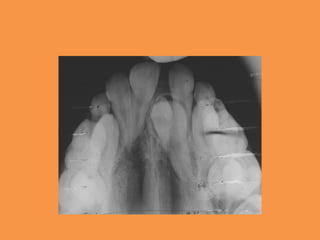

Figure 2: Preoperative maxillary

occlusal radiograph

Figure 2: Preoperativemaxillary occlusal radiograph

Fig.2 Panoramic radiographshowing impacted maxillary central incisor and mesiodens in region of 21